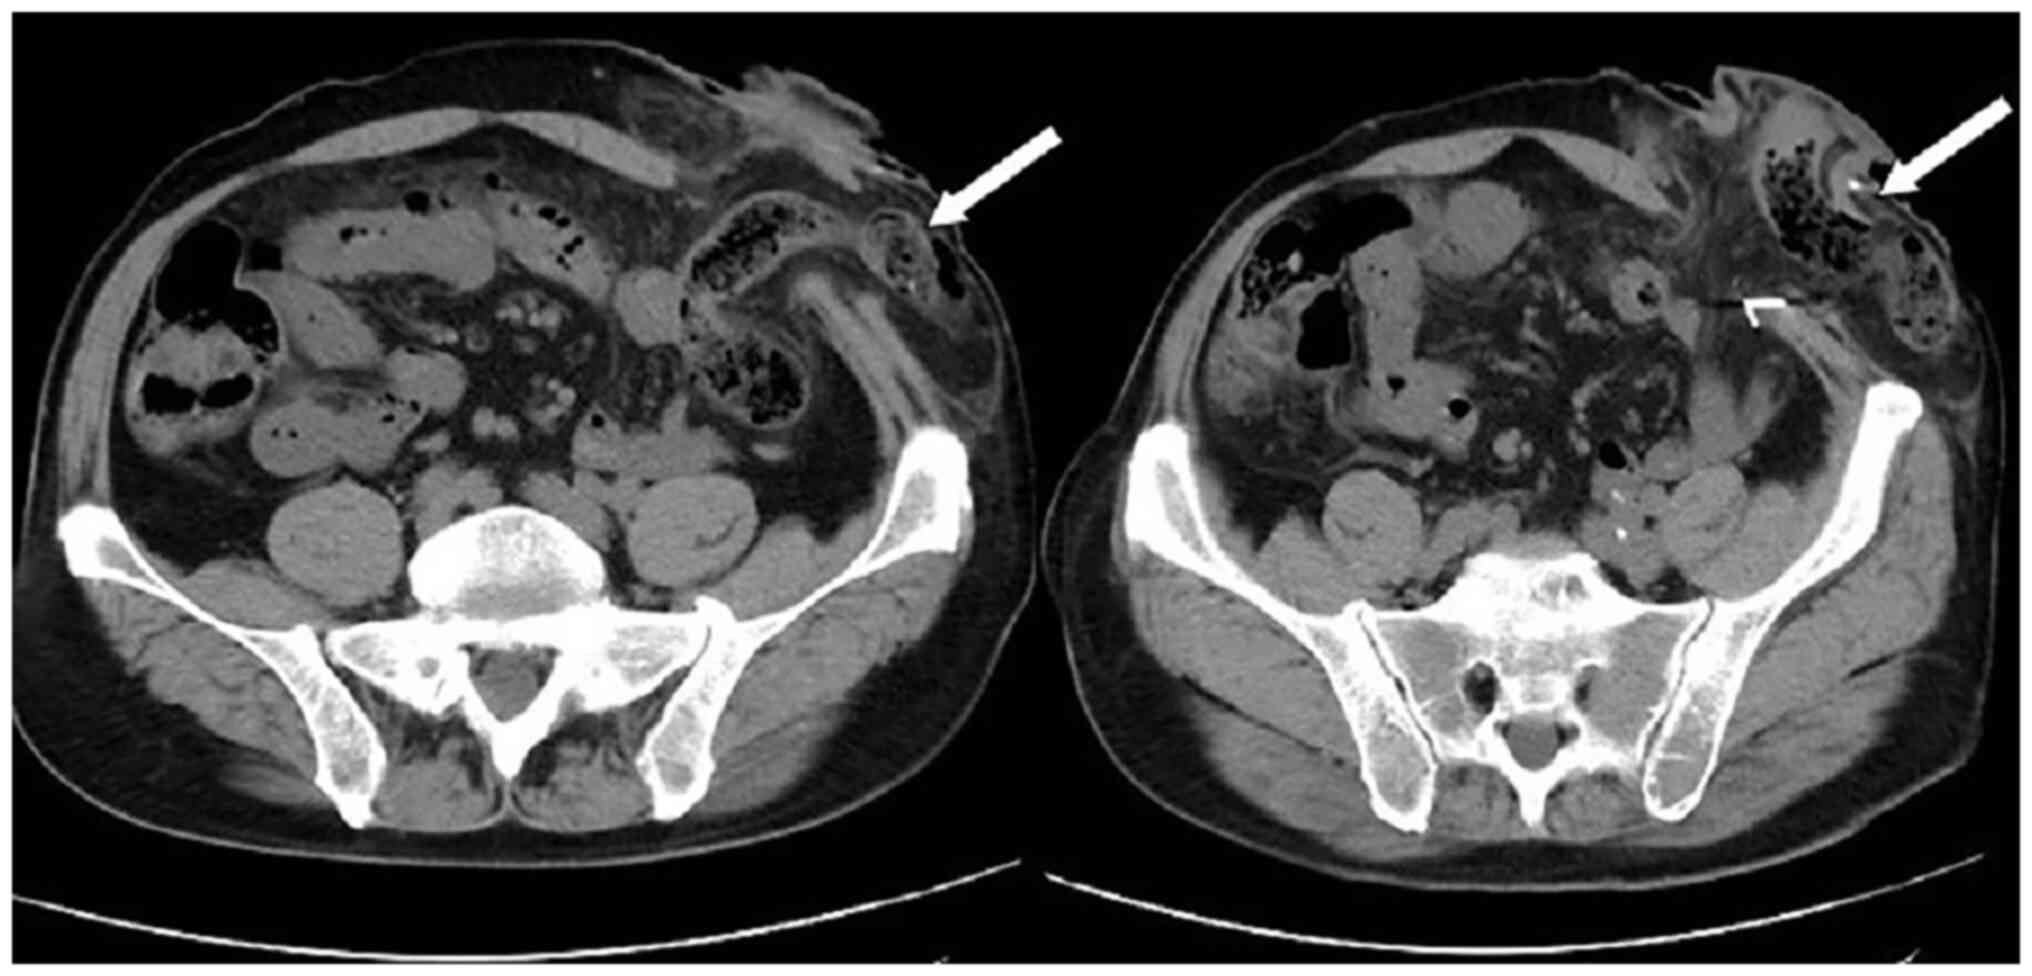

Subsequently, the patient presented with a lump around the colostomy stoma site and intermittent abdominal pain in November 2020. Physical examination revealed a lump measuring ~10×10 cm around the stoma, which did not reduce in size when the patient was lying flat. Abdominal CT (Fig. 4) revealed that the intestinal tube had protruded into the subcutaneous fat layer of the abdomen. Based on the patient's medical history, physical examination (a lump around the colostomy stoma site) and the result of abdominal CT (Fig. 4), a parastomal hernia was suspected. Surgery was the recommended treatment. Routine preoperative blood tests, coagulation function, and liver and kidney functions showed no abnormalities. Parastomal hernia repair surgery was performed using the keyhole technique in November 2020. A relatively soft drainage tube was placed subcutaneously in the surgical area. The patient recovered well after the surgery and was discharged on the third postoperative day without removing the drainage tube. During discharge, the surgical area was not compressed. However, five days after discharge, the patient experienced swelling, pain and bleeding at the surgical site. Abdominal CT showed a hematoma in the surgical area (Fig. 5). After taking hemostatic treatment measures (hemostatic drugs, compression hemostasis), fresh blood still slowly flowed out from the drainage tube. Dynamic reexamination of coagulation function showed that it gradually deteriorated, and the activated partial thromboplastin time was gradually delayed to 60 sec, which was 20 sec longer than normal (reference range, 20–40 sec). The patient had stubborn anemia, and after multiple blood transfusions, no significant increase was identified in hemoglobin, which remained between 45–68 g/l (normal range, 130–175 g/l). A bone marrow biopsy was also performed to investigate the cause of persistent bleeding (Fig. 6). The bone marrow smear was stained using the Wright staining method and 200 cells were counted under a microscope. The results showed abnormal proliferation of plasma cell lines in bone marrow smears, accounting for 35% of total cells, with an immature plasma cell composition accounting for 21.0% of total cells (normal range, 0–0.8%). This result is consistent with the diagnosis of multiple myeloma (10,11). Fig. 6 shows the characteristics of abnormal plasma cells: This type of cell was significantly different in size, with the cell body and nucleus appearing circular, elliptical, ovoid or irregular in shape. The nucleus was misaligned, the chromatin of the nucleus appeared as a granular or loose network and certain cells showed obvious nucleoli. The cytoplasm was rich, stained opaque dark blue and flame-like, with obvious light staining bands around the nucleus. Nodular protrusions and vacuoles were easily observed, while no particles were seen. The morphological features were consistent with those of MM (10). Further testing revealed elevated serum immunoglobulin A (IgA) levels of 76.7 g/l (normal range, 0.82–4.53 g/l) and significantly increased serum β2 microglobulin (β2-microglobulin) levels of 16,205 ng/ml (normal range, 604–2,286 ng/ml). Based on the results of the bone marrow puncture, the bone destruction, anemia and bleeding were attributed to MM. After consultation with a hematologist, the patient was diagnosed with MM (IgA-λ type, Durie-Salmon Stage III). The Durie-Salmon staging system is a classic staging system for MM. The staging criteria for Stage III are as follows: One or more of the following abnormalities must be present: Hemoglobin <8.5 g/dl; serum calcium >12 mg/dl; very high myeloma protein production; IgG peak >7 g/dl; IgA peak >5 g/dl; Bence Jones protein >12 g/24 h; and >3 lytic lesions on bone survey (11). The patient was transferred to the hematology department and was treated with the PCD regimen (bortezomib, cyclophosphamide, dexamethasone), chemotherapy and blood transfusion. The specific dosage of medication is calculated based on the patient's body surface area. One chemotherapy cycle is 4 weeks and this patient received 6 cycles of chemotherapy. Afterwards, the patient received maintenance treatment with bortezomib monotherapy. The seventh rib lesion invaded the surrounding soft tissue, and the interventional department performed an empty needle puncture biopsy on it. The pathological and immunohistochemical results of the puncture tissue are consistent with multiple myeloma (10). The lesion was determined to be plasmacytoma, suggesting involvement of MM (Fig. 7), and the immunohistochemical results were as follows: CD138 (+), CD38 (+), cytokeratin (CK) (−), Ki67 (15%, +), Lambda (+) and MM oncogene 1 (+) (Fig. 8). CK negativity indicated the absence of malignant cells of epithelial origin. The patient's condition gradually improved, with increasing hemoglobin levels, recovering coagulation function, absorption of the hematoma around the stoma (Fig. 9) and alleviation of bone pain. For the past 2 years, the patient has been regularly treated in the hematology department and the progression of the MM has been slow (Figs. 10 and 11). Fig. 10 is a PET/CT image of the patient diagnosed with MM one year later. The arrows in Fig. 10 indicate the metabolic status of the lesionsin the right seventh posterior rib, upper sternum, and first lumbar spine. The increased metabolism of these three main lesions is consistent with the manifestation of MM. In Fig. 11, row A represents the situation of lesion in the upper sternum at different time-points; row B shows the situation of lesion in the upper sternum at different time-points; and row C shows the situation of lesion in the upper sternum at different time-points. The arrows in Fig. 11Aa, Ba and Ca refer to the lesions of the upper sternum, the seventh rib on the right side and the first lumbar vertebra when MM was diagnosed. Fig. 11Ab-Cb shows the respective lesions 1 year after the diagnosis of MM and Fig. 11Ac-Cc shows them at 2 years after the diagnosis of MM. After comparison, the progression of these three lesions was not obvious. After treatment, the soft tissue mass around the lesion of the right seventh rib gradually became smaller. The patient has not experienced any worsening bone pain symptoms since being diagnosed with MM. The patient has been regularly visiting the hematology outpatient department. During the follow-up period, the patient's blood routine, coagulation function and serum immunoglobulin are being tested every two months, and chest CT and spinal CT examinations conducted every 6 months. During follow-up, there has been occasional mild anemia but no coagulation abnormalities.

Figure 5.

Hematoma in the surgical area with a visible drainage tube in the surgical area (the large arrow represents a hematoma and the small arrow represents a drainage tube).